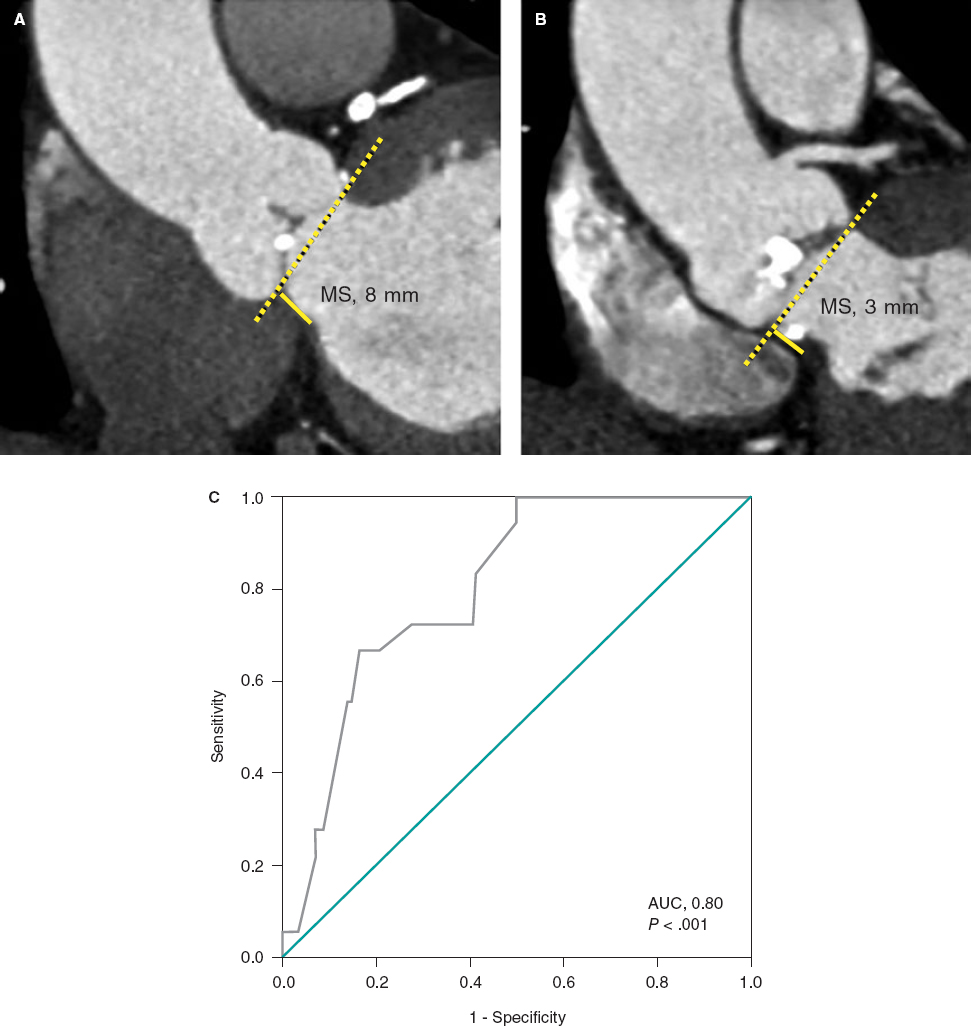

6. When the desired position has been achieved, the clip opens and perpendicularity is assessed. This should be done by using a 2D TEE in the transgastric short axis or by 3D zooming in the atrial view. The clip should be rotated smoothly so that it remains completely perpendicular to the desired grasping site (figure 6 and video 3 of the supplementary data).

Figure 6. With the clip on the tricuspid annulus the transgastric short axis (A) or 3D zoom (B) should be used to steer the clip. A, anterior; Ao, aorta; S, septal.